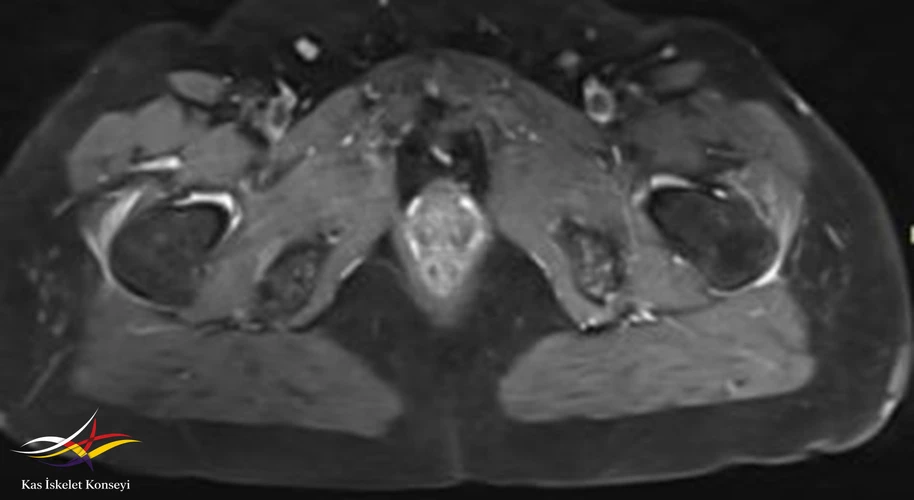

İncelemeler: Lomber MRG: L4-5 diskal bulging ve sol foraminal stenoz var. Kalça MRG istendi, iki yanlı trokanterik bursit rapor edildi.

Tedavi için öncelikle trokanterik bursa enjeksiyonları öngörüldü. Bu tedaviden alınacak yanıt görüldükten sonra mevcut lomber patolojisinin (foraminal stenoz) tekrar değerlendirilmesi önerildi. İki yanlı belirgin trokanterik bursit görülmesi nedeniyle polimyalgia romatika açısından da incelenmesi önerildi.